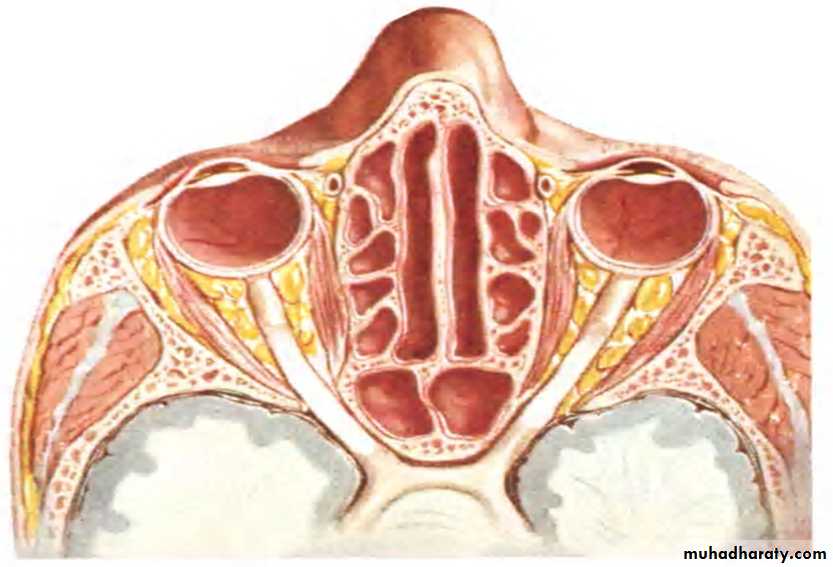

MAXILLARY SINUS:

Largest of allPyramidal in shape

Base pointing to lateral wall of nose.

Apex laterally in the zygomatic process of maxilla.

BOUNDARIES:

Anterior:- facial surface of maxillaPosterior:-infratemporal and pterygopalatine fossa

Medial:- middle and inferior meatus

Floor:- alveolar and palatine processes of maxilla

Roof:-floor of orbit